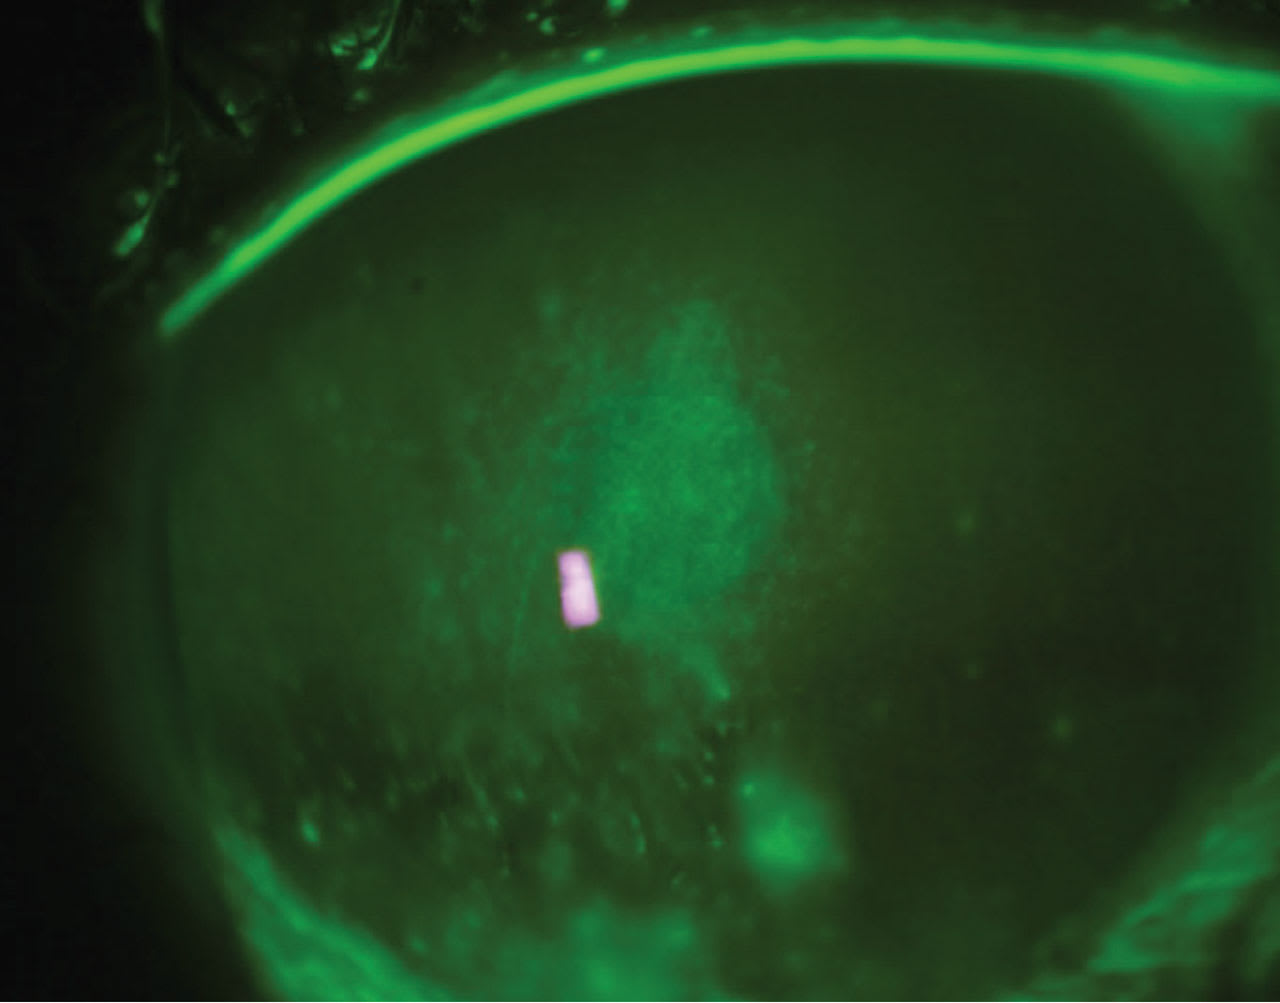

A 44-year-old male presented to the clinic with a chief complaint of severe pain, along with photophobia in his right eye for the past few days.

• Patient ocular history: ectasia secondary to laser-assisted in situ keratomileusis (LASIK) surgery for the past few years. The patient admitted to sleeping in his scleral contact lenses. Figure 3 displays the anterior segment image.

• Diagnosis:

1) corneal ulcer

2) ectasia

• Treatment: Approaching a compromised cornea with underlining conditions such as keratoconus or post-refractive complications must be aggressive but guarded. In this case, it was a cryopreservative slim-profile amniotic membrane, besifloxacin q.i.d. to the affected eye, and artificial tears every 30 minutes. Figure 4 shows the eye with an AMCL over the compromised cornea. Figure 5 shows an image three days after removal.